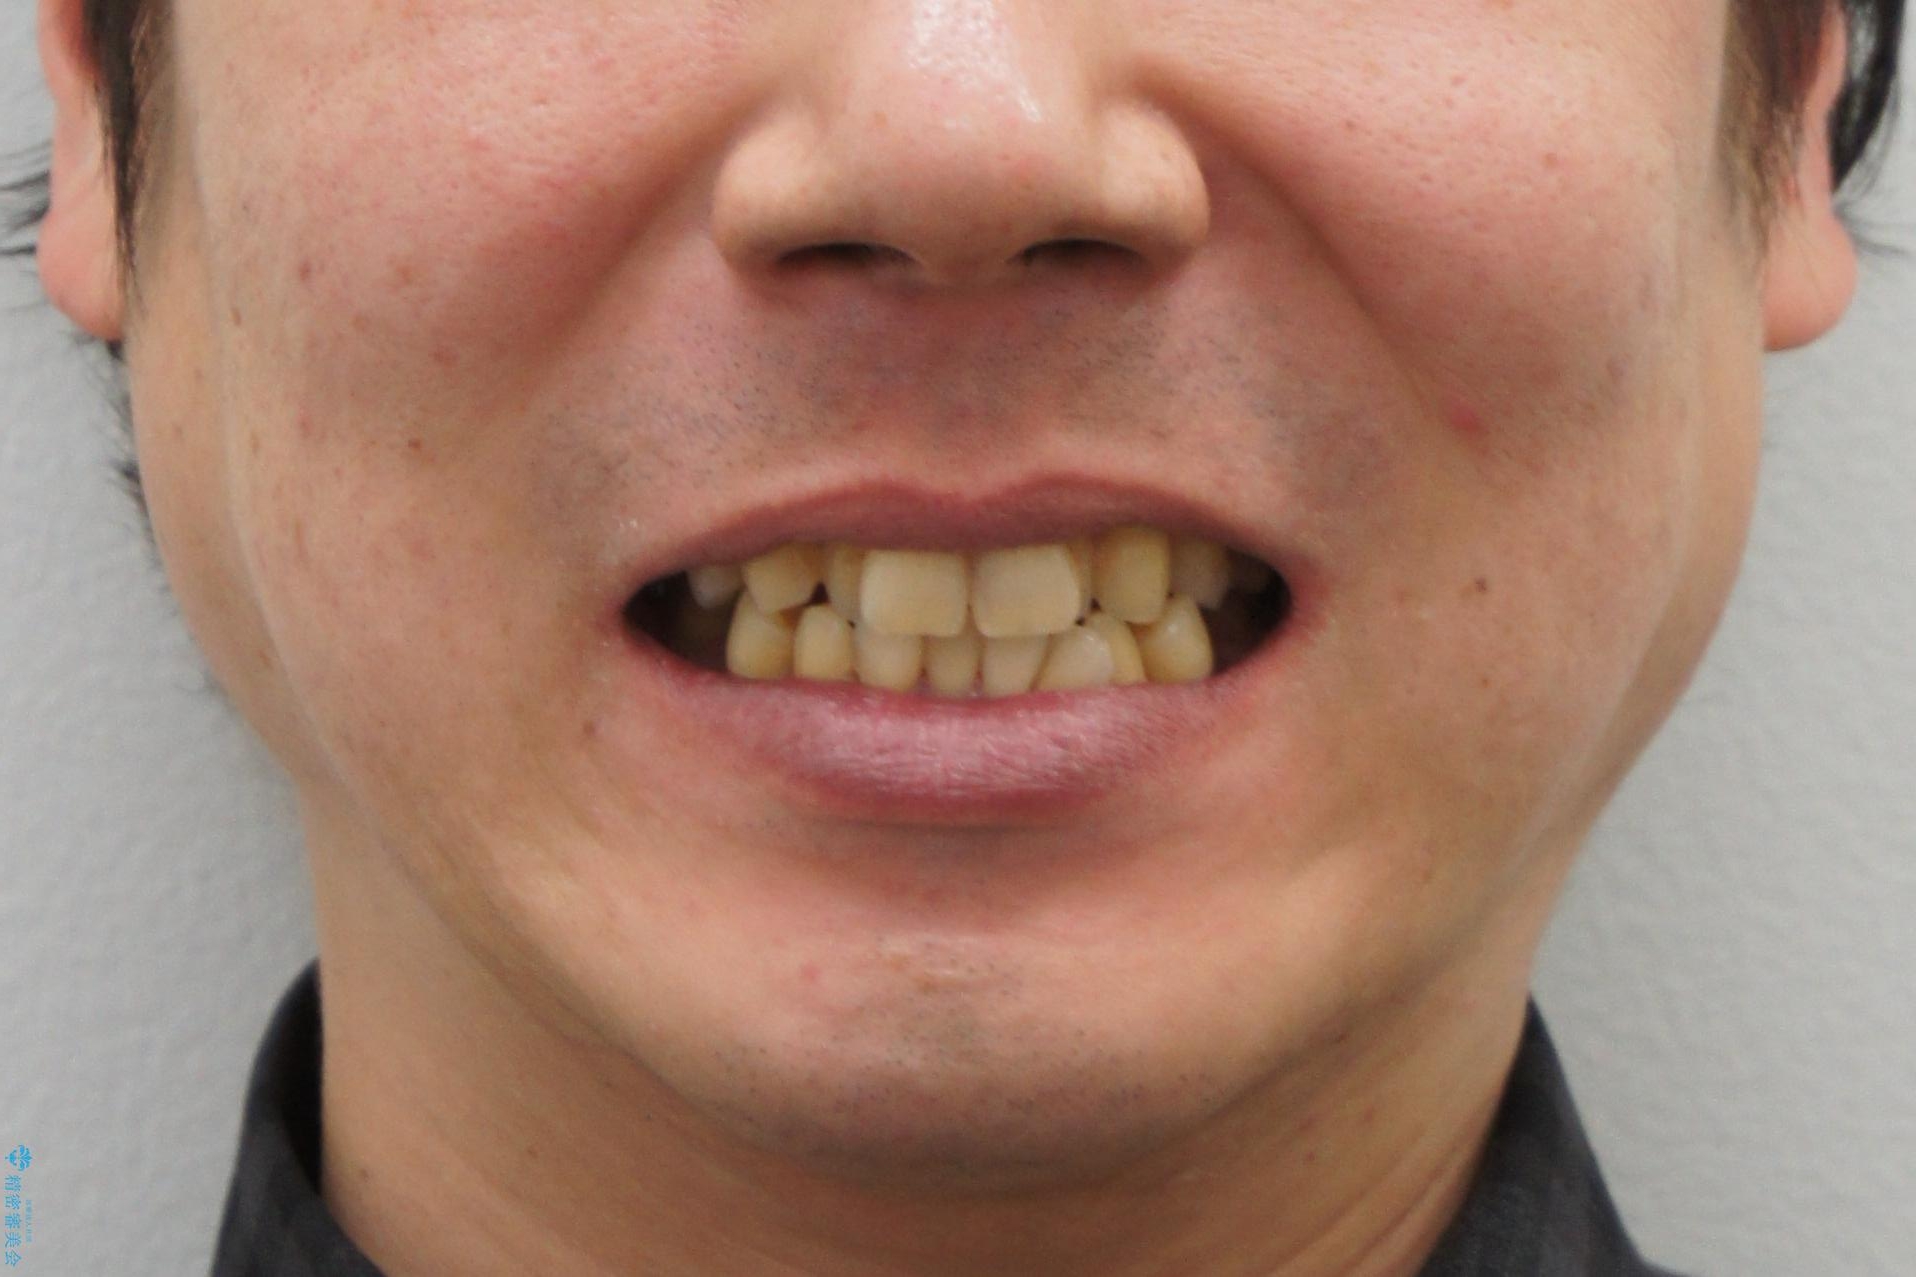

- 30代男性

- 前歯の重なったところが虫歯になり、物理的にアプローチが難しい状態でした。

矯正治療前に虫歯を取り、歯並びが良くなってから本格的にセラミック治療を行いました。